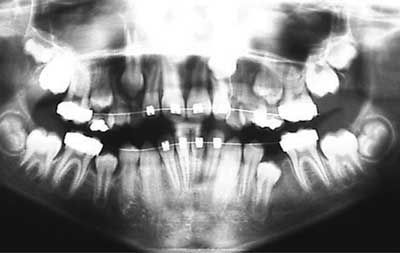

No hubo recurrencia de imágenes radiolúcidas en ninguna de las radiografías postquirúrgicas durante el seguimiento periódico de los pacientes. Tres (3) pacientes fueron seguidos por 7 años y uno de ellos tenía la lesión más abajo de la región cervical del primer molar inferior permanente no erupcionado y ahora está completamente en oclusión pero tuvo que ser ayudado con ortodoncia. (PACIENTE #1)

Cuatro (4) pacientes fueron evaluados por 5 años, dos (2) pacientes por 3 años 9 meses y tres (3) pacientes por 2 años y 6 meses. Todos los casos mostraron buena formación ósea alrededor del diente involucrado con la lesión y completa erupción de la dentición permanente. Los dientes erupcionados mostraron adecuada vitalidad pulpar y llegaron a ocluir correctamente. Dos (2) de los pacientes necesitaron tratamiento ortodóncico para corregir su maloclusión sin extracciones.

Foto 7: Rx Post 01-2003

Foto 8-2: Rx Post 07-2004